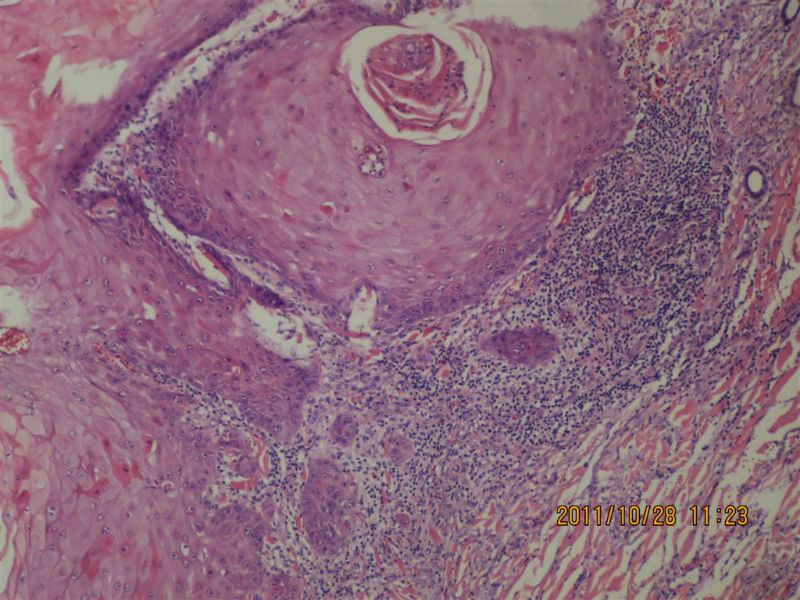

女性,71岁,右前臂肿物。角化棘皮瘤还是高分化鳞癌?

• 女性,71岁,右前臂肿物。角化棘皮瘤还是高分化鳞癌?图1

• 女性,71岁,右前臂肿物。角化棘皮瘤还是高分化鳞癌?图2

我觉得基底部还是有一些突破的,更倾向高分化鳞癌!

不知道肿物的生长速度怎样?活动度?低倍看火盆样外观、唇样边缘,底部较平整,无明显突破。更趋向于角化角化棘皮瘤。

低倍镜见表皮呈火山口样,内充满角质团块,周边上皮增生呈衣领样,底部表皮增生呈假上皮瘤样,上皮角不规则延伸至真皮,真皮大量炎细胞浸润.